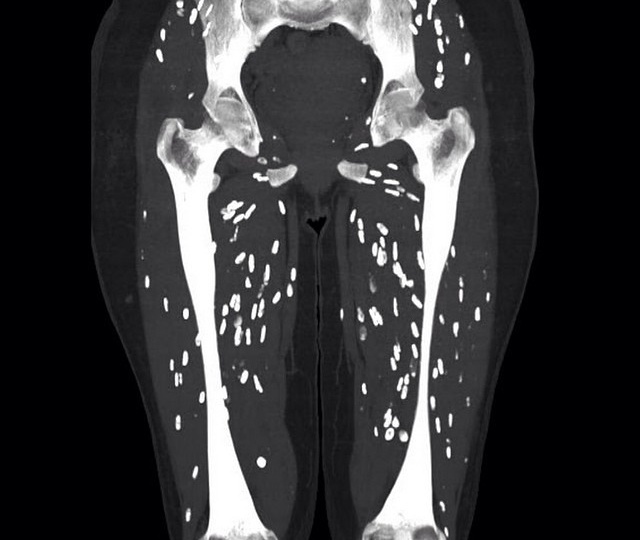

Употребление в пищу сырого или недостаточно термически обработанного мяса и рыбы — серьёзный риск заражения паразитами. Они могут вызывать тяжёлые заболевания с осложнениями вплоть до угрозы жизни. Разберёмся, какие паразиты передаются таким путём, как проявляются вызванные ими болезни и как их предотвратить. Первые симптомы могут появиться через несколько дней или месяцев после употребления заражённого продукта. Типичные проявления: При длительном течении развиваются осложнения: гиповитаминозы, поражение печени, сердца, нервной системы. Для выявления паразитов применяют: Чтобы избежать заражения, соблюдайте правила: Важно: при появлении симптомов после употребления сырого мяса/рыбы обратитесь к врачу. Самолечение опасно — препараты против паразитов токсичны и назначаются строго по результатам диагностики. Не забудьте подписаться, то бы не пропустить все самое интересное и ПОЗНАВАТЕЛЬНОЕ!!! Читайте так же: